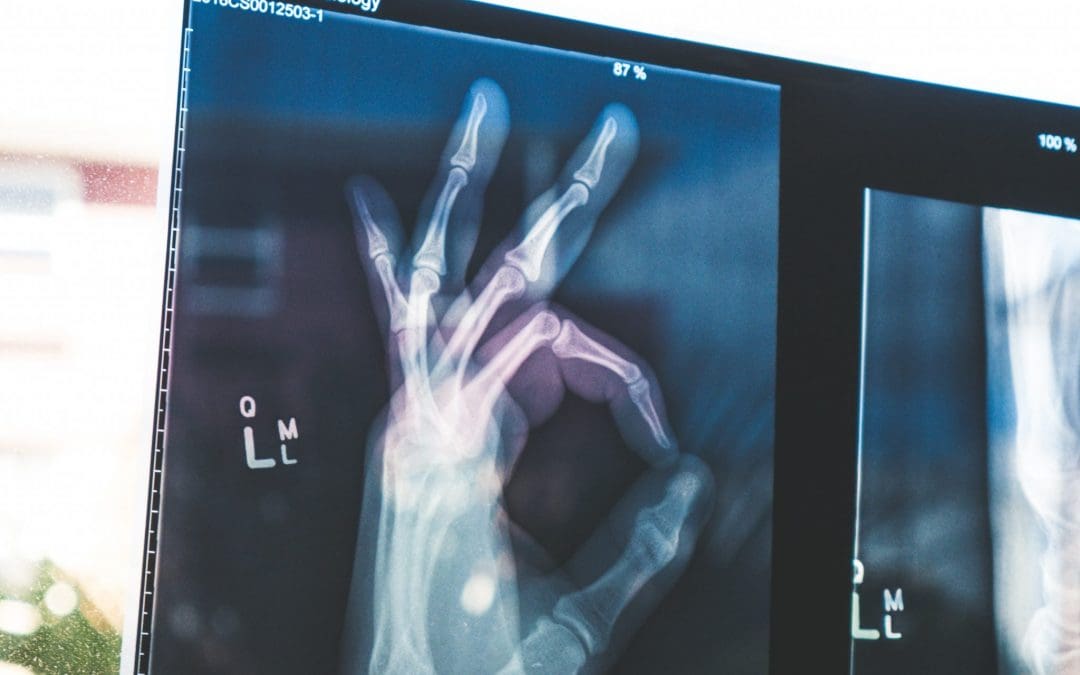

Osteoporosis is a progressive metabolic bone disease characterised by the loss of bone mineral density (BMD) and compromised bone strength. Osteopenia is considered a halfway point to osteoporosis; the bone density is lower than normal and treating it may slow the progressive bone loss that leads to osteoporosis.